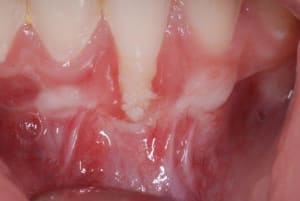

PRE-OP_GREFFE_002_vmfrhj.jpg